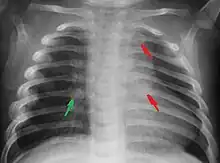

Most nations with child abuse laws deem the deliberate infliction of serious injuries, or actions that place the child at obvious risk of serious injury or death, to be illegal.[36] Bruises, scratches, burns, broken bones, lacerations—as well as repeated "mishaps", and rough treatment that could cause physical injuries—can be physical abuse.[37] Multiple injuries or fractures at different stages of healing can raise suspicion of abuse.

C. Henry Kempe and his colleagues were the first to describe the battered-child syndrome in 1962.[40] The battered-child syndrome is a term used to describe a collection of injuries that young children sustain as a result of repeated physical abuse or neglect.[41][42] These symptoms may include: fractures of bones, multiple soft tissue injuries, subdural hematoma (bleeding in the brain), malnutrition, and poor skin hygiene.[42][43]

The immediate physical effects of abuse or neglect can be relatively minor (bruises or cuts) or severe (broken bones, hemorrhage, death). Certain injuries, such as rib fractures or femoral fractures in infants that are not yet walking, may increase suspicion of child physical abuse, although such injuries are only seen in a fraction of children suffering physical abuse.[90][91] Cigarette burns or scald injuries may also prompt evaluation for child physical abuse.[92]

- Shaken baby syndrome. Shaking a baby is a common form of child abuse that often results in permanent neurological damage (80% of cases) or death (30% of cases).[93] Damage results from intracranial hypertension (increased pressure in the skull) after bleeding in the brain, damage to the spinal cord and neck, and rib or bone fractures.[94]